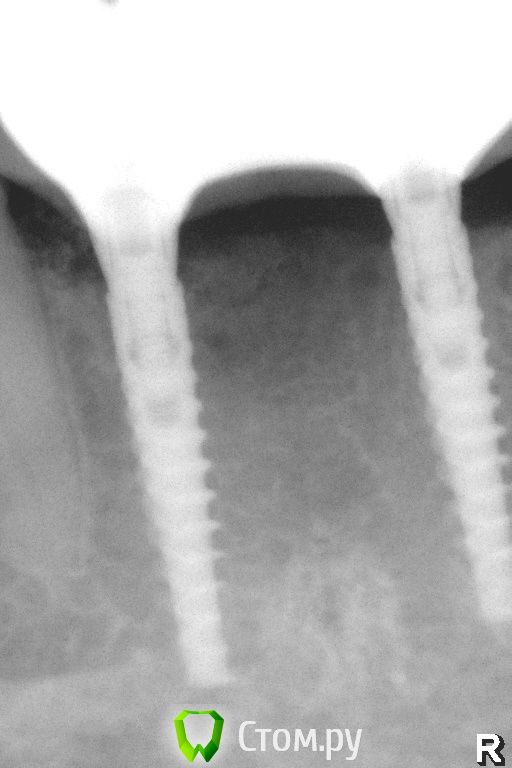

Pavel-Pskov Опубликовано 4 ноября, 2014 Автор Поделиться Опубликовано 4 ноября, 2014 Еще пара снимков.Через год. Ссылка на комментарий

Pavel-Pskov Опубликовано 6 ноября, 2014 Автор Поделиться Опубликовано 6 ноября, 2014 подскажите, почему при такой толщине не поставить 3.75?НА медиальных 2-3 витка вестибулярно были не в кости , пришлось подсыпаться под ламину. Ссылка на комментарий

pigmaleon Опубликовано 4 ноября, 2014 Поделиться Опубликовано 4 ноября, 2014 подскажите, почему при такой толщине не поставить 3.75? Ссылка на комментарий